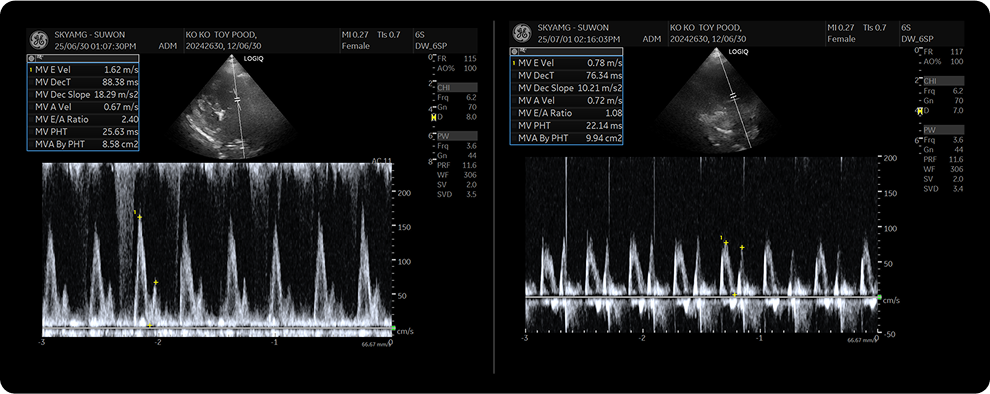

일반적으로 검진 혹은 진료 시에 청진을 하여 심잡음을 확인하고, 흉부 방사선 검사를 통해 외관상의 심장 형태를 평가 하게 됩니다.

이후로 심장 내강의 형태와 기능 등을 확인하기 위한 심장 초음파 검사를 진행하여, 심장의 구조와, 판막상태, 혈류 역류 및 기능등을 정밀하게 평가하여 심장 상태를 진단하게 됩니다.